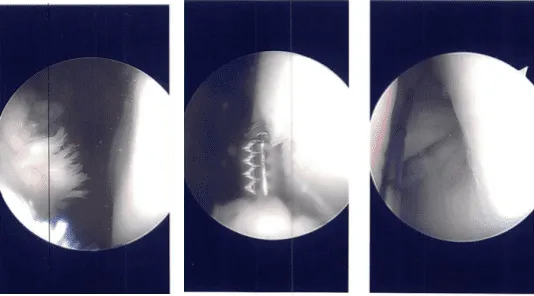

Se construyó un plano entre el poplíteo y el gastrocnemio con los recipientes detrás. El espéculo de Sims se utilizaba para retraer los vasos hacia atrás. Se reintrodujo otro endoscopio en el borde lateral y la reparación integral se realizó usando FasT-Fix con un implante curvo entero interno y suturas curvas Nephew.

Tres de ellos se colocaron en la parte posterior y medial del cuerpo al músculo poplíteo y uno se colocó lateralmente al músculo poplíteo. La reducción y reparación resultaron ser adecuadas. Se liberó el torniquete y se encontró un buen coágulo de sangre en su interior.